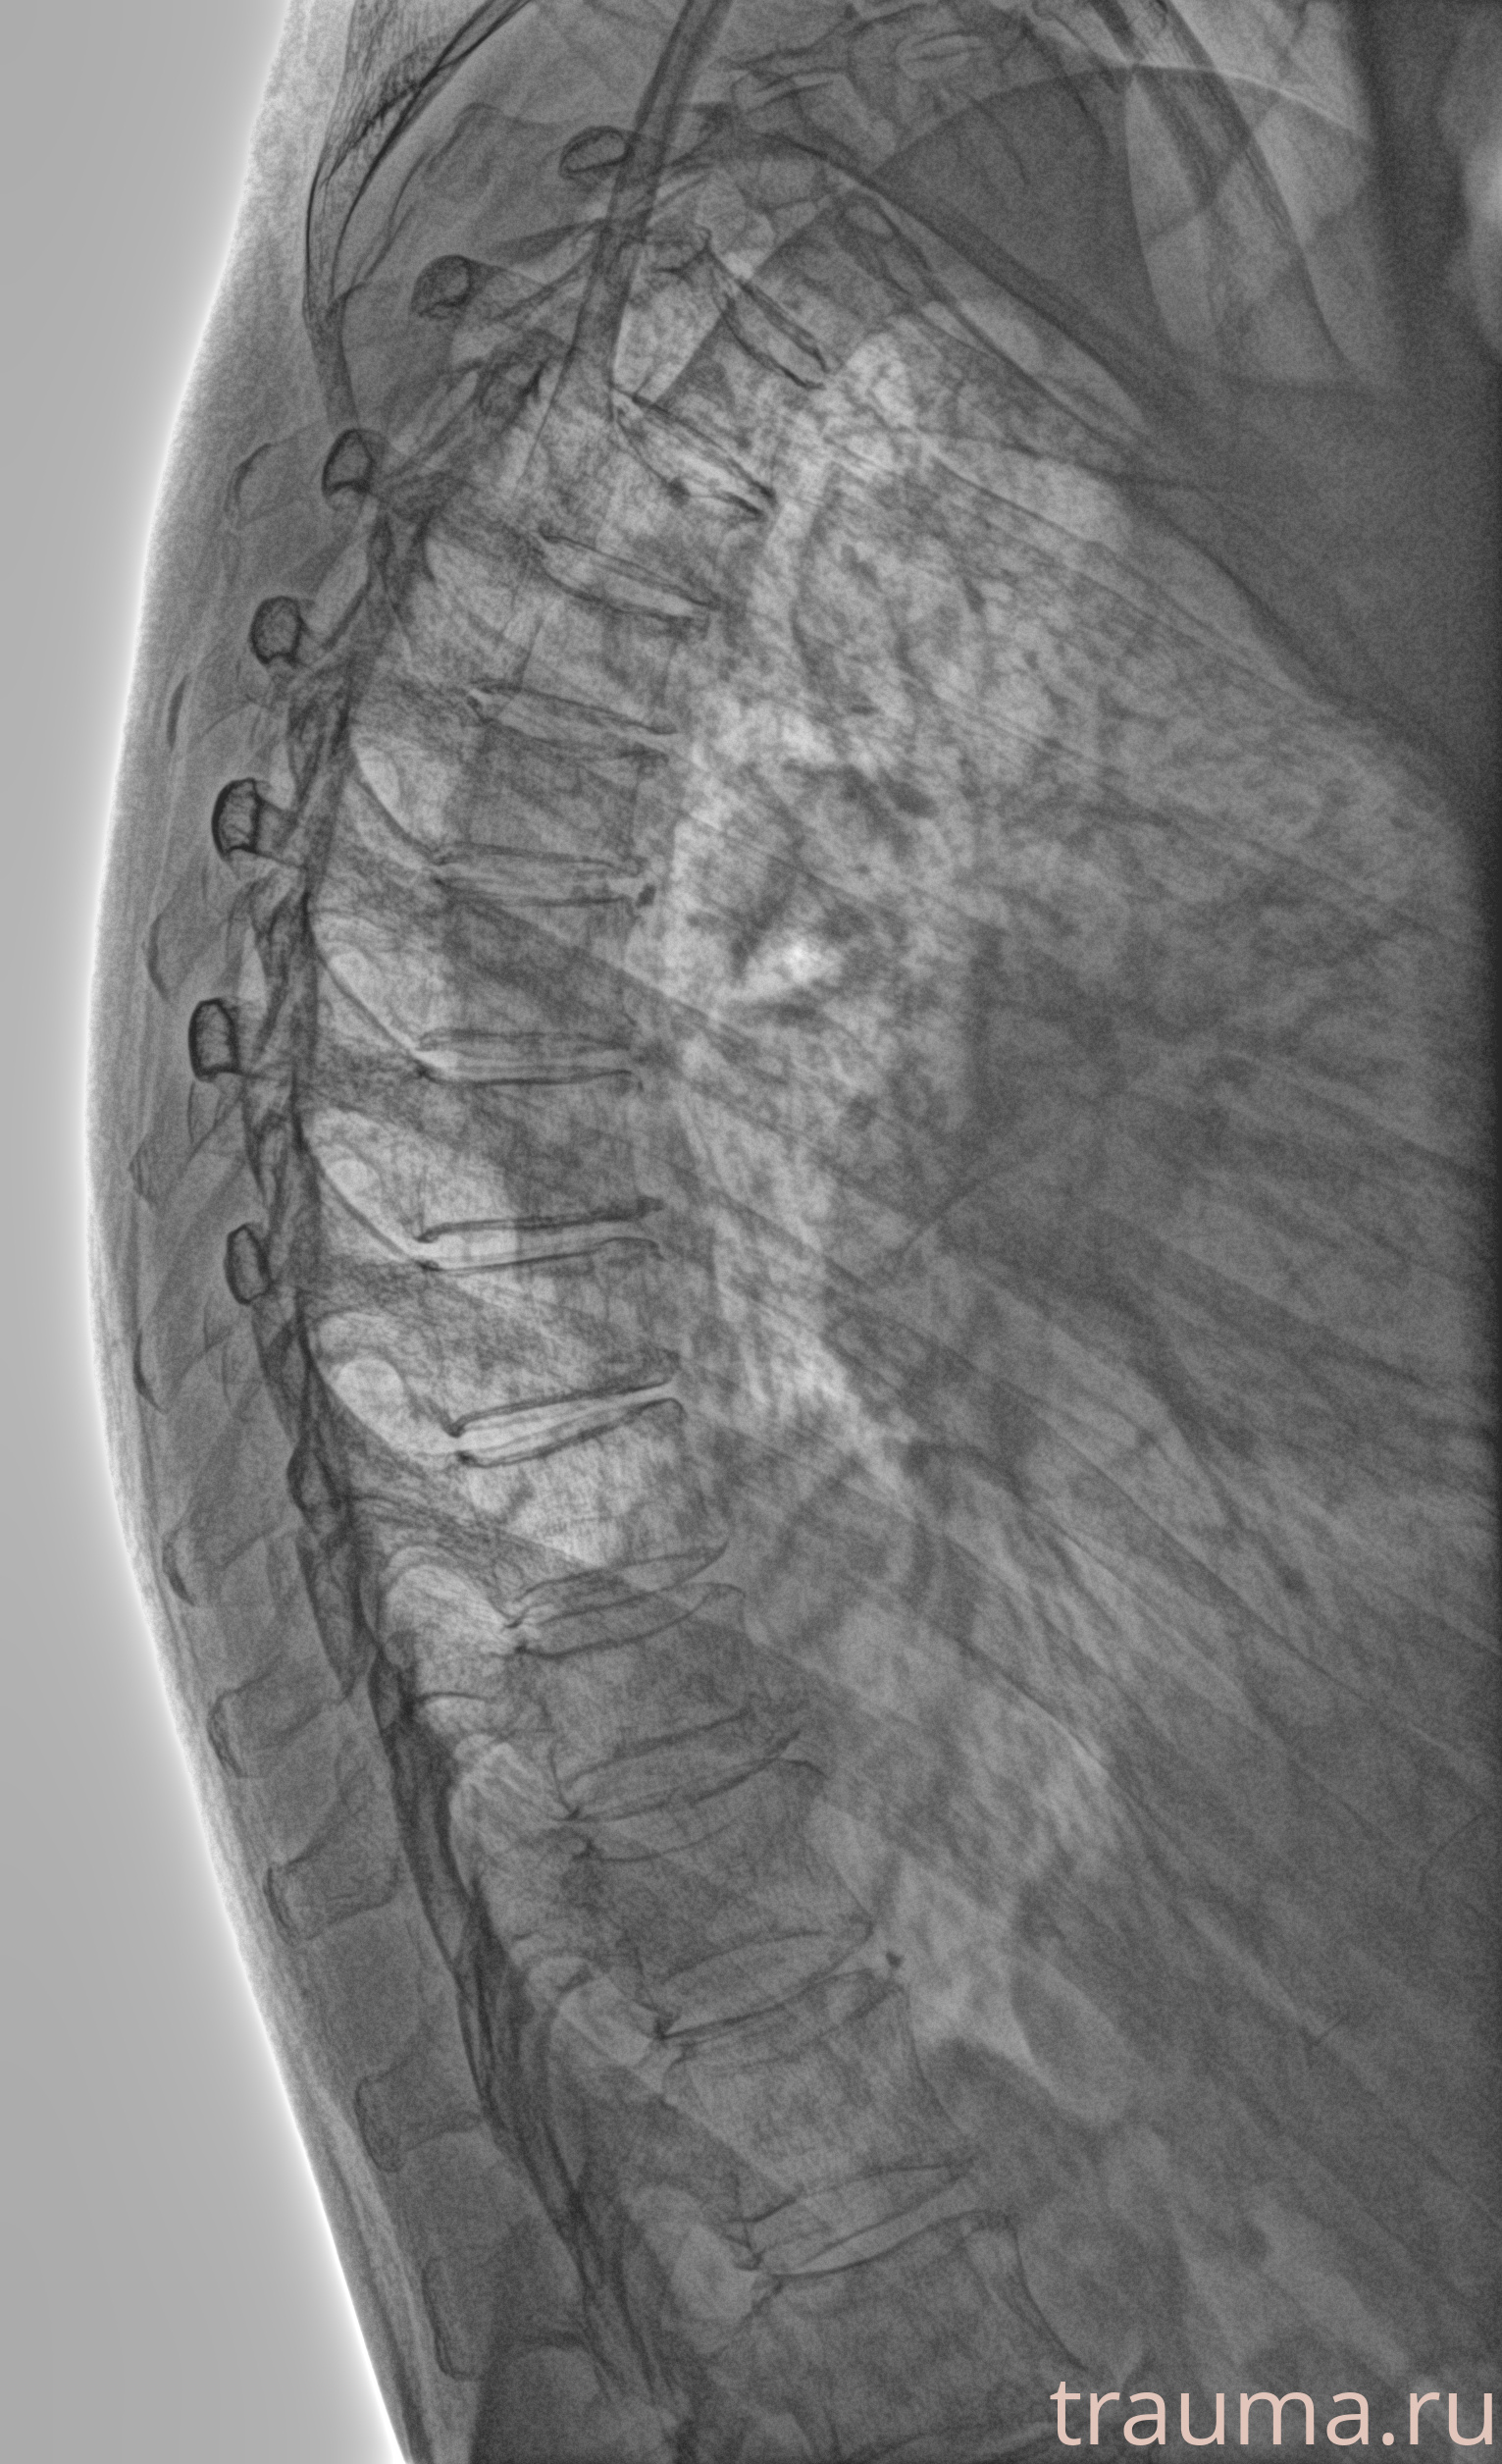

Рентген на дому: по вашему адресу приезжает врач-рентгенолог, травматолог-ортопед с мобильным рентгеновским аппаратом, проводит диагностику травмы или заболевания, делает необходимые рентгенограммы, дает рекомендации по дальнейшему лечению. Получить качественные снимки в домашних условиях возможно благодаря уникальной методике, разработанной МосРентген Центром для института  Склифосовского